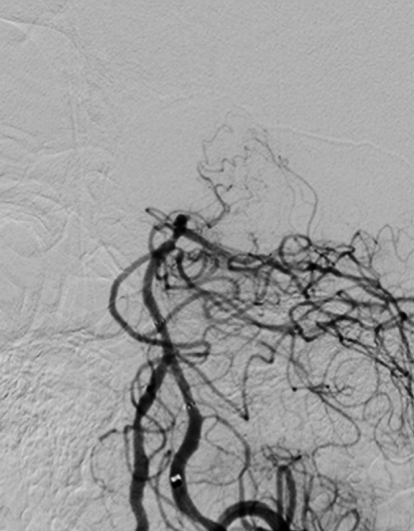

图片5.jpg  图片6.jpg 图片7.jpg

大脑中动脉取栓前                                         大脑中脉取栓中                                                            大脑中动脉取栓后